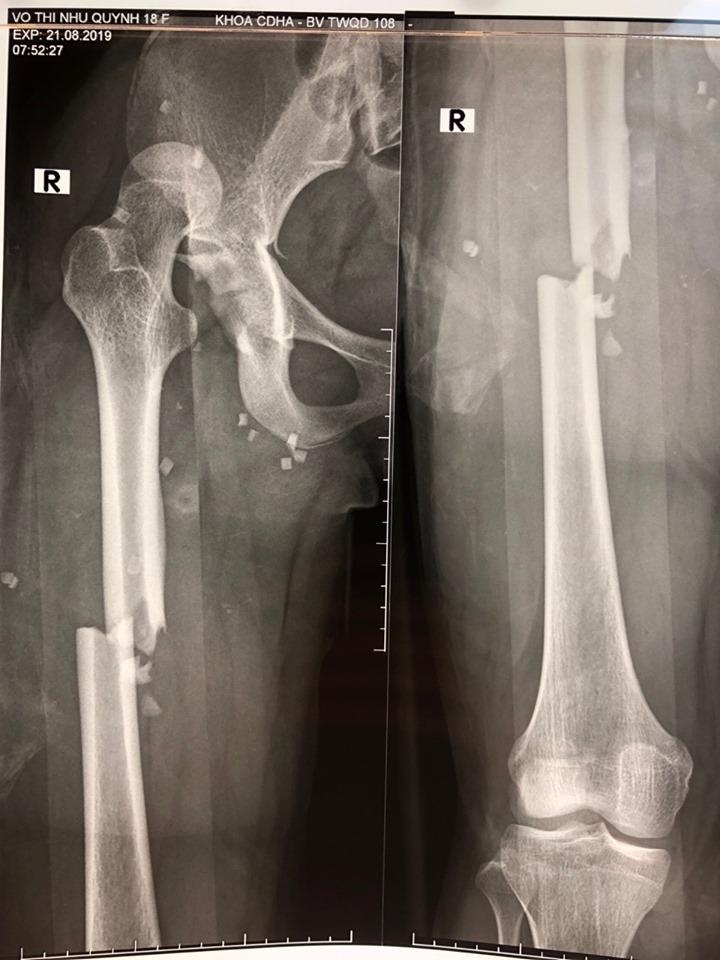

| Hình ảnh X-quang gãy xương đùi của bệnh nhân. Ảnh: Sức Khỏe Đời Sống. |

Bệnh nhân Q. được chuyển đến Bệnh viện Trung ương Quân đội 108 sau tai nạn giao thông giờ thứ sáu với tình trạng đa chấn thương: Gãy khung xương chậu, trật khớp háng phải. Đồng thời, chân phải của Q. gãy hở hai chỗ, máu chảy nhiều, chân trái cũng bị gãy xương đùi.

Các bác sĩ chẩn đoán sơ bộ bệnh nhân bị sốc chấn thương, gãy khung xương chậu: Gãy cánh xương cùng trái và sai khớp cùng chậu phải di lệch; gãy ngang ổ cối, sai khớp háng phải; gãy hở 1/3 giữa xương đùi phải, sai khớp hở khớp sên chày kèm gãy xương sên phải, gãy kín 1/3 giữa xương đùi trái do tai nạn giao thông.